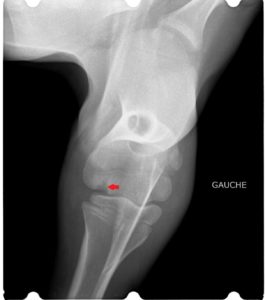

Le cas décrit ici est celui d’ une petite génisse Prim’Holstein de moins d’un mois. Elle avait une arthrite du coude, probablement faisant suite à une entérite (voir radiographies et échographie de l’articulation).